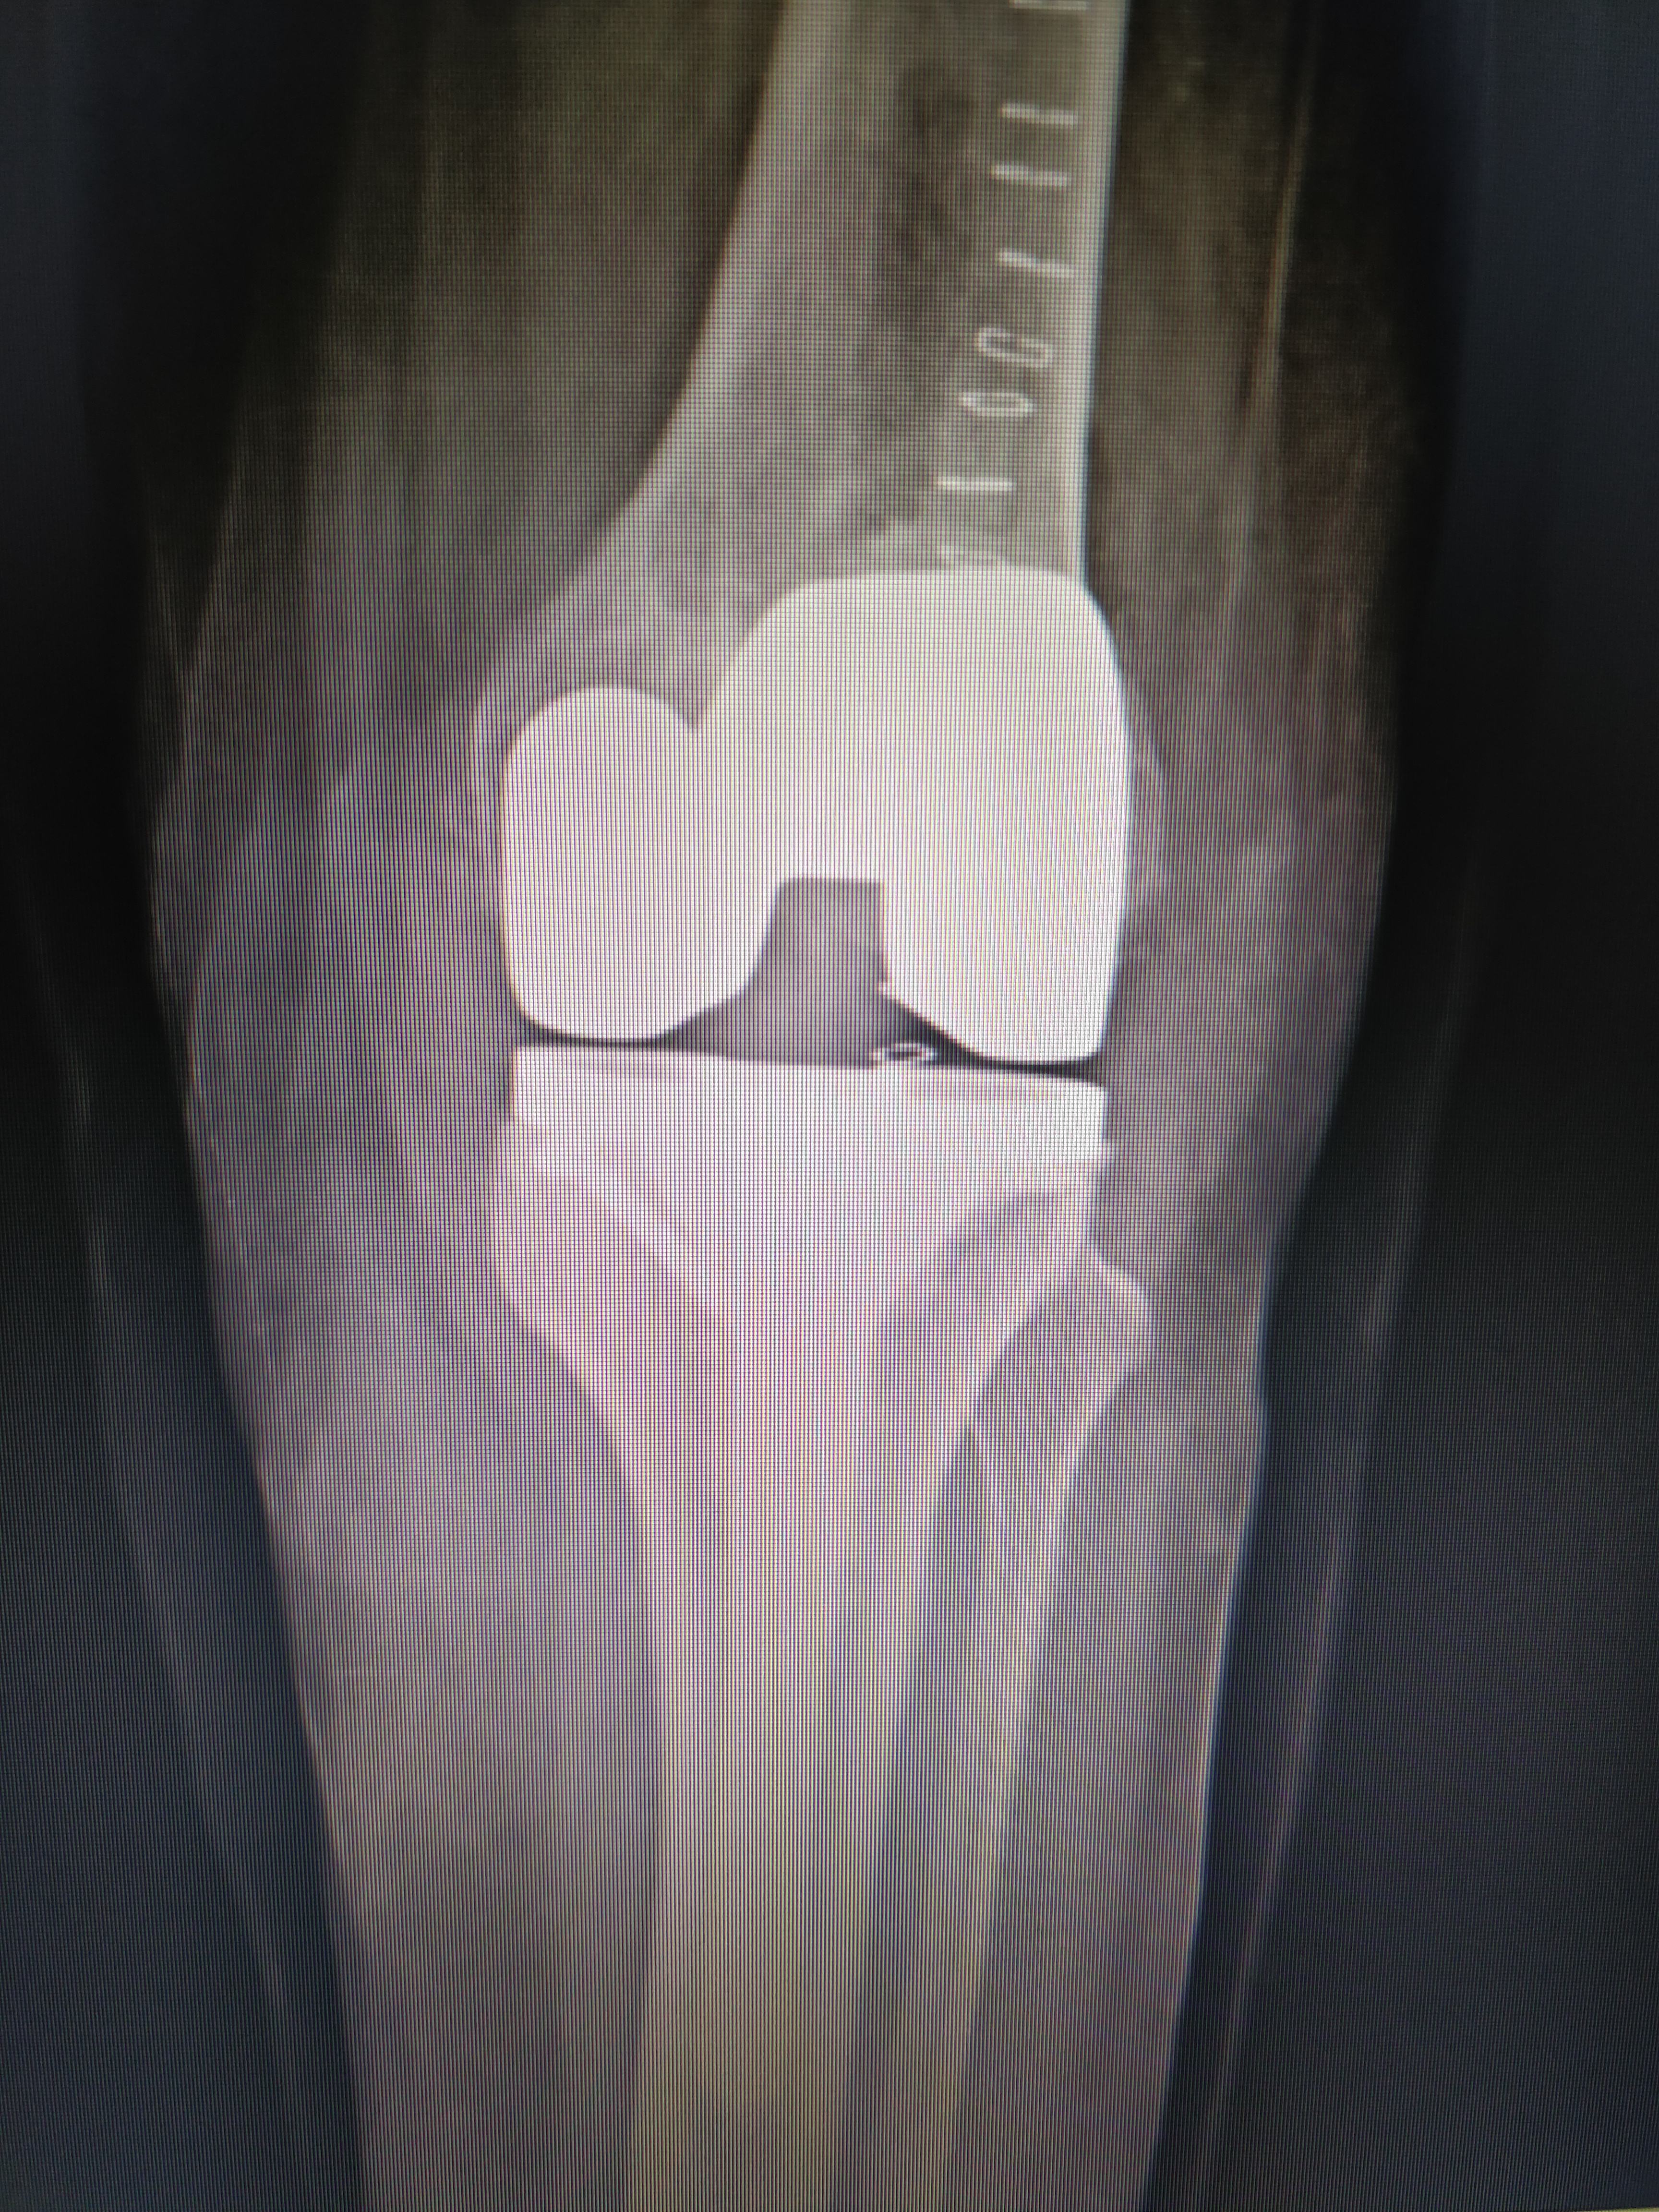

Dr. Nilesh Hirekhan Orthopedic specializes in orthopedic surgery with a focus on joint replacement, sports medicine, and trauma surgery.

Dr. Nilesh Hirekhan treats a wide range of orthopedic conditions including arthritis, fractures, ligament injuries, tendonitis, and joint disorders.